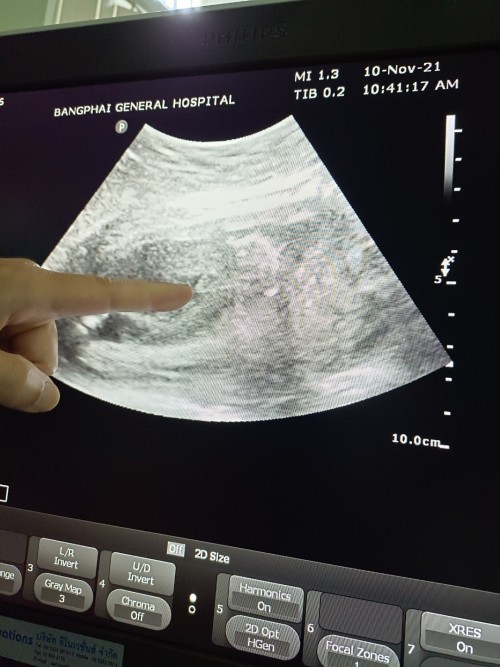

ท้อง3 ได้ผู้ชายสมใจแล้วคับ ☺️